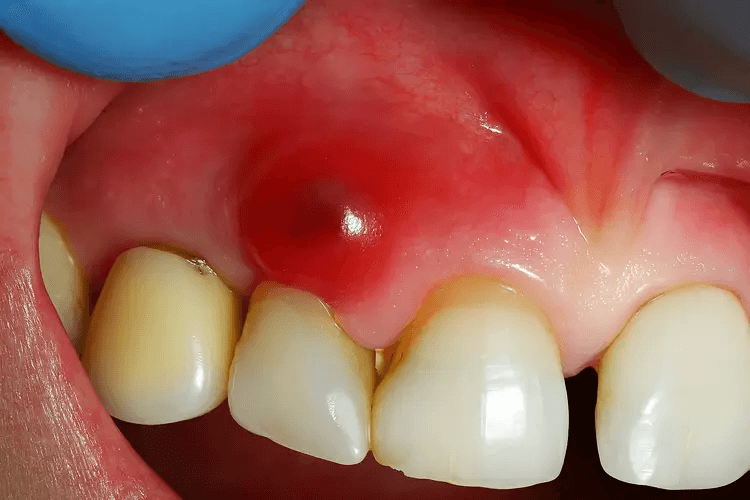

Una cisti è una cavità nell’osso o nei tessuti molli, rivestita da cellule e di solito piena di liquido o di materiale semiliquido. Nell’area delle mascelle, le cisti ai denti si sviluppano di solito vicino all’apice della radice del dente oppure intorno a un dente incluso.

È importante distinguere una cisti da un ascesso. L’ascesso è un’infezione acuta con pus e spesso con dolore intenso. Una cisti, all’inizio, può svilupparsi senza dolore, ma con il tempo può danneggiare l’osso, spostare i denti e favorire l’infiammazione.

• Gonfiore della gengiva o un “rigonfiamento” nella zona del dente.